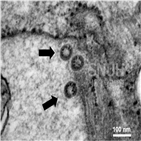

이날 처음으로 코로나19 바이러스가 에어로졸 형태로 화장실의 하수도를 거쳐 전파할 수 있다는 전문가들의 경고와 우려를 공식 인정했다. 이는 2003년 사스(SARS·중증급성호흡기증후군) 당시 홍콩의 아모이가든 아파트에서 감염자가 용변을 보고 물을 내린 뒤 바이러스가 포함된 에어로졸이 배수구 등으로 퍼지면서...

고농도의 에어로졸에 노출된 상황"이라고 설명했다. 에어로졸 전파는 2003년 사스(SARS·중증급성호흡기증후군) 당시 홍콩의 아모이가든 아파트 집단 감염 사태의 원인으로 추정된다. 이 때문에 전문가들은 에어로졸 전파 위험을 경고해왔다. 아울러 중국 당국은 코로나19 환자에 대한 '혈장(血漿) 치료'가 효과가...